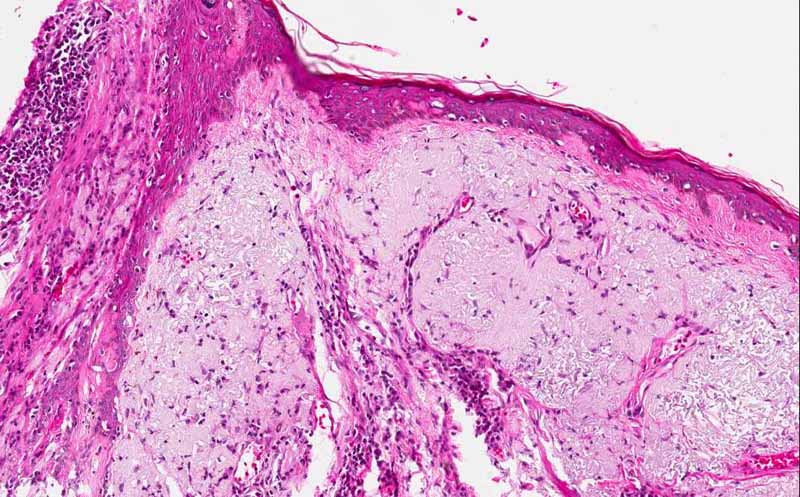

Hematoxylin & eosin

Area 2: This is taken at the junction between the tumor and the adjacent skin uninvolved by the carcinoma. There is a thick layer of bluish mucoid appearing material in the dermis of the uninvolved skin. These changes are what is termed solar elastosis and is indicative of sun damage. It is typically seen in sun exposed skin.